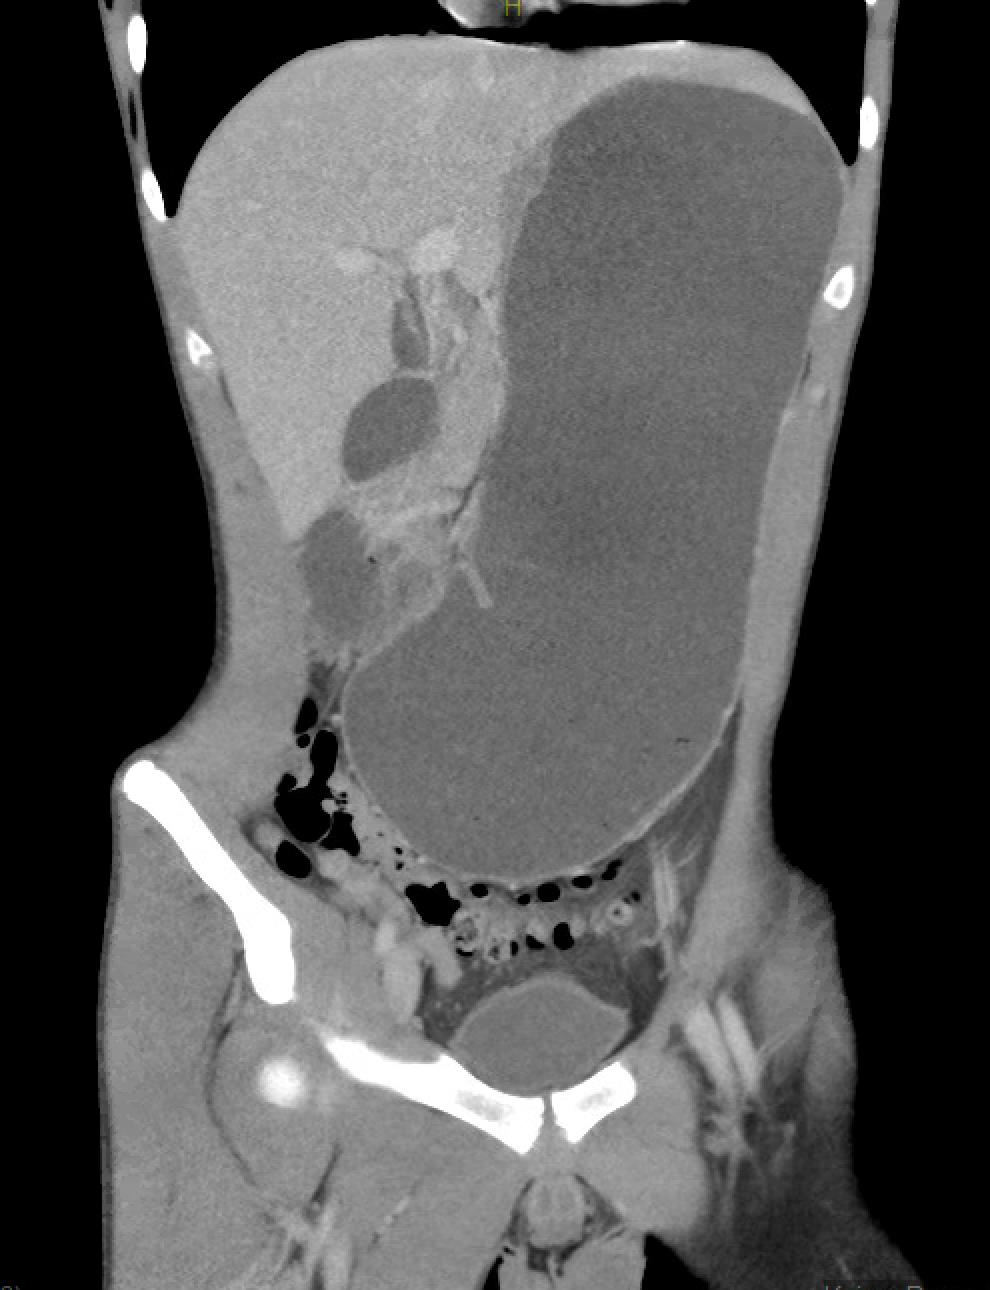

Abdominal computed tomography angiography during hospitalization

FINDINGS (abbreviated): Normal robust enhancement of abdominal aorta, origins of celiac, superior mesenteric and renal arteries are demonstrated. The aortomesenteric angle measures 14 degrees. The aortomesenteric distance at the level of the duodenal crossing is 6 mm.

IMPRESSION:

- Interval resolution of previously demonstrated marked distention of the stomach. Proximal duodenum is mildly dilated, but significantly improved compared to prior.

- Both the aortomesenteric angle and aortomesenteric distance are decreased, as may be seen with SMA syndrome. Clinical correlation and follow-up care are recommended.

- Left chest tube is present with small left pneumothorax.

- Subcutaneous air is present with soft tissues in the lower chest.

- Small amount of posterior pneumomediastinum is present.

- Mild splenomegaly is present. The spleen appears elongated and relatively thin transversely.